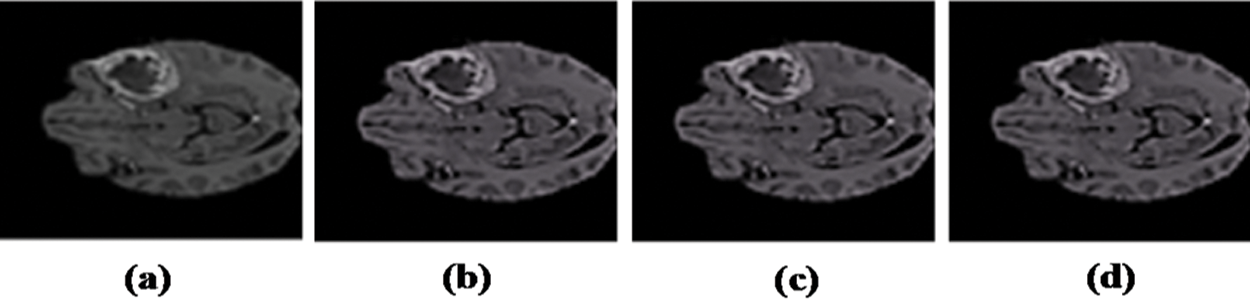

After the image is acquired, preprocessing is applied. For image enhancement, a median filter is applied, and level set method is used for bias field correction [53]; then connected component analysis of ground truth is done to find the largest connected object, which gives the location information of tumor, i.e., (x, y, w, h).

Figure 2: Resulted images after Preprocessing: (a) Input image with artifacts. (b) Image after bias field correction. (c) Median filter applied. (d) Resultant preprocessed image

The above box plot shows the DSC score of each patient. It also gives the highest and lowest DSC score range. For P1, which represents Patient 1, the minimum DSC score is 0.3, and the maximum DSC score is more than 0.8. Similarly, it gives the maximum and minimum range of the DSC. However, in a few images, the brain tumor was not localized accurately by RCNN because of the complex brain structure and visual similarity between tumor and non-tumor regions. The False positive MRI slices that were not detected correctly because of the complex brain structure are shown in Fig. 2, which illustrates the difficulty in brain tumor detection. In Tab. 2, we depict DSC scores for each of the selected ten patients along with true positive and true negatives; at the end of the table, we also represent average results for DSC. The highest DSC score was of P4 and P7 of 1, while P10 shows the least DSC score. Fig. 4 represents the boxplot of DSC of all ten patients. Fig. 5 shows the heat map of all ten patients with HGG.